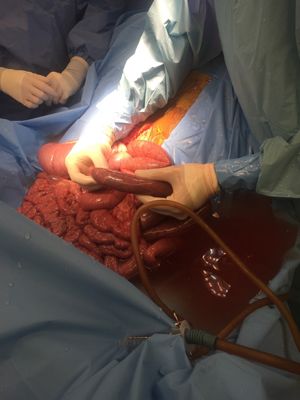

A colic surgery being performed at Rood & Riddle Saratoga.“They got the foal to our facility within about 40 minutes,” Tull says. “The foal was quite painful when it arrived. Rapid evaluation and triage was performed and, based on the history of significant abdominal pain, with multiple loops of distended small intestine apparent on ultrasound, exploratory laparotomy was recommended.

“Exploratory surgery demonstrated a small intestinal volvulus, which occurs when the small intestine twists around its mesentery, the tissue that connects it to the internal body wall and, more importantly, carries the blood supply,” Tull continues. “The small intestine was carefully untangled to correct the volvulus. The contents of the small intestine were then pushed back into the cecum where there was room for the ingesta to pass on through the GI tract. After we were satisfied with the success of that portion of the procedure, we continued exploring the GI tract and completely lavaged it with several liters of sterile fluid. The abdomen was closed routinely.”

Luckily in this particular patient there was no compromised small intestine from loss of blood supply requiring removal of intestine. “The major reason we were able to obtain a good outcome in this particular foal was how rapidly the initial colic signs were identified, and how quickly the referring veterinarian sent the foal in to the hospital,” Tull says. “From start of colic signs to surgical intervention was less than two hours. That can make a big difference.” The foal recovered well and was home again five days after surgery.